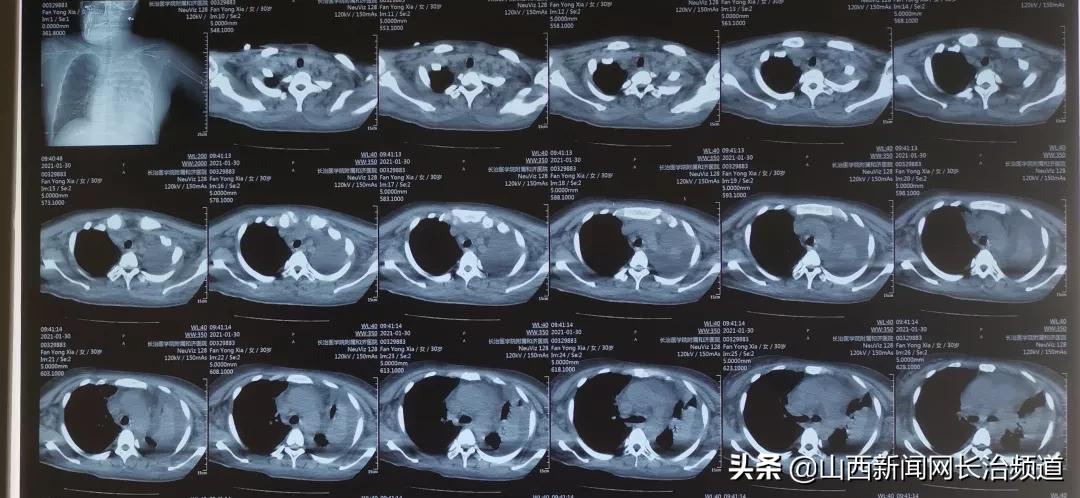

入院后患者病情进行性加重,血肌酐持续升高,短时间内出现脑出血、继发性癫痫、痰栓,病情危重,暂停肾活检穿刺术检查。

左肺痰栓